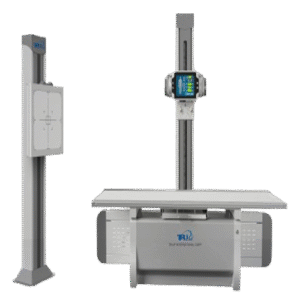

Shoimage 630mA Floor-Mounted Digital Radiography System

Shoimage 630mA Floor-Mounted Digital Radiography System – Model: SHO-DDX03

The Shoimagem SHO-DDX03 is a 630mA floor-mounted digital radiography system tailored for high-volume diagnostic centers and modern hospitals that demand speed, precision, and power. Engineered with a high-frequency 630mA generator and a high-resolution digital flat panel detector, this system delivers crystal-clear radiographic images with rapid acquisition time and optimized patient safety.

With a user-friendly interface, automated positioning, and DICOM-ready workflow, the SHO-DDX03 redefines how radiology departments approach diagnostic efficiency.

Category: Advanced Digital Radiography

Product Type: Floor-Mounted DR System

Model: SHO-DDX03

X-ray Output: 630mA High-Frequency Generator

Brand: Shoimagem

Technology: Fully Integrated DR System with High-Powered X-ray Unit

Availability: In Stock

Installation & Training: Available Across Bangladesh